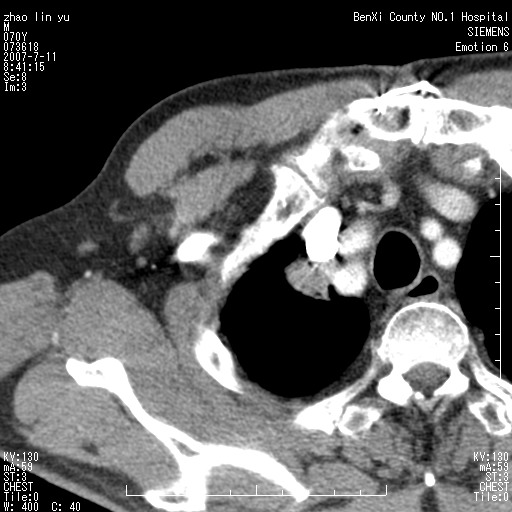

以下是引用王靖旗在2007-7-10 17:12:00的发言:[br] 男、70、咳嗽两个月,半年前换瓣手术,胸片未见异常,于昨天行x片发现右肺上野大片影,行ct扫描,这里是减薄图像,余肺正常。明天晚上会有增强扫描片,到时我会上传。[br][br] 冠状位请大家细看,应该是有意义的,[br][br] 请大家先看平扫发表意见。[br][br]